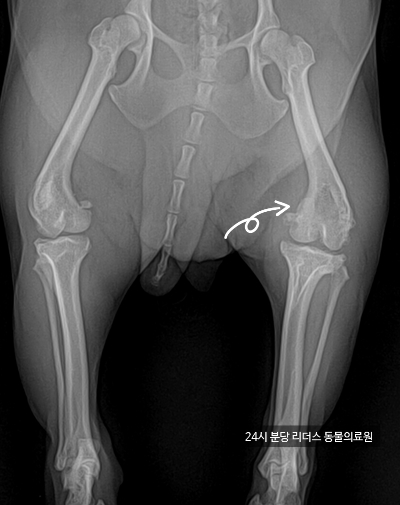

슬개골은 강아지 무릎 앞쪽에 있는 작은 뼈로, 이게 제자리를 벗어나면서 통증과 움직임에 문제가 생기는 걸 **‘슬개골 탈구’**라고 해요. 탈구는 보통 안쪽으로 발생하고, 견종에 따라 유전적 요인도 크게 작용해요. 특히 푸들, 말티즈, 치와와 같은 소형견이 잘 걸리죠.

3. 무조건 수술해야 할까?

모든 슬개골 탈구가 수술 대상은 아닙니다. 보통은 1~2단계 정도면 비수술적 관리로도 충분히 생활이 가능하고,

3단계 이상일 경우나 통증, 염증, 보행 장애가 심할 경우에만 수술을 고려해요. 수의사 진단을 통해 단계 확인 → 그에 맞는 관리 플랜이 필요합니다.